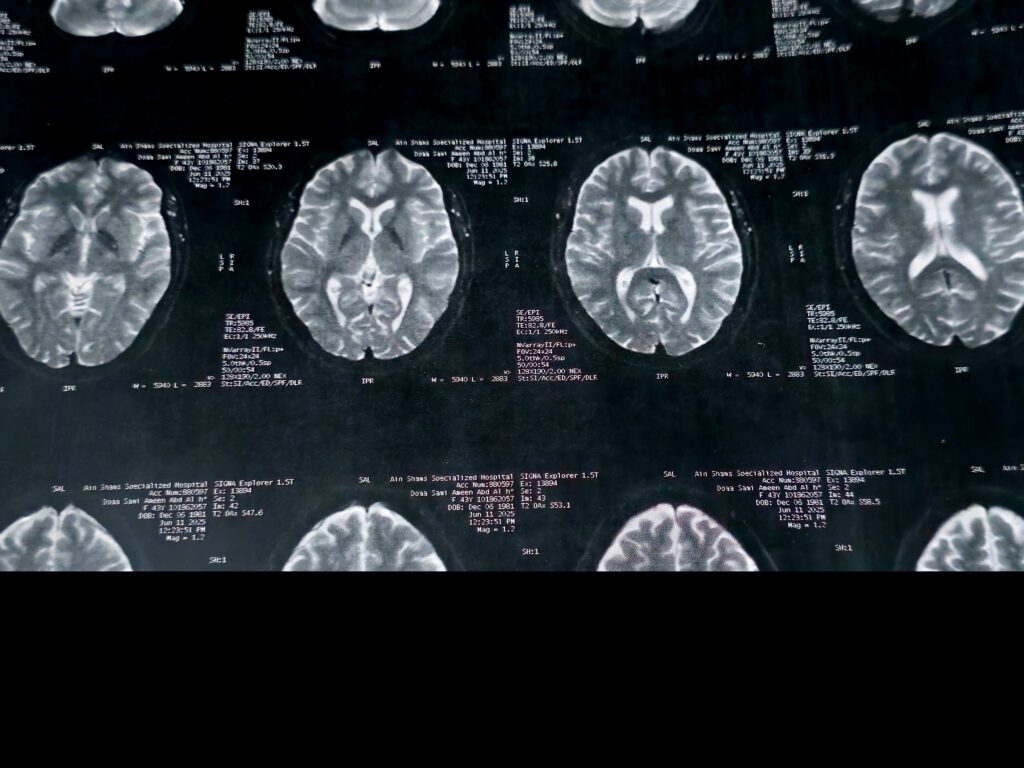

The study, which analysed brain scans from nearly 4,000 people ranging from infancy to 90 years old, found that brain development follows five distinct “epochs,” separated by four key turning points at roughly ages 9, 32, 66 and 83.